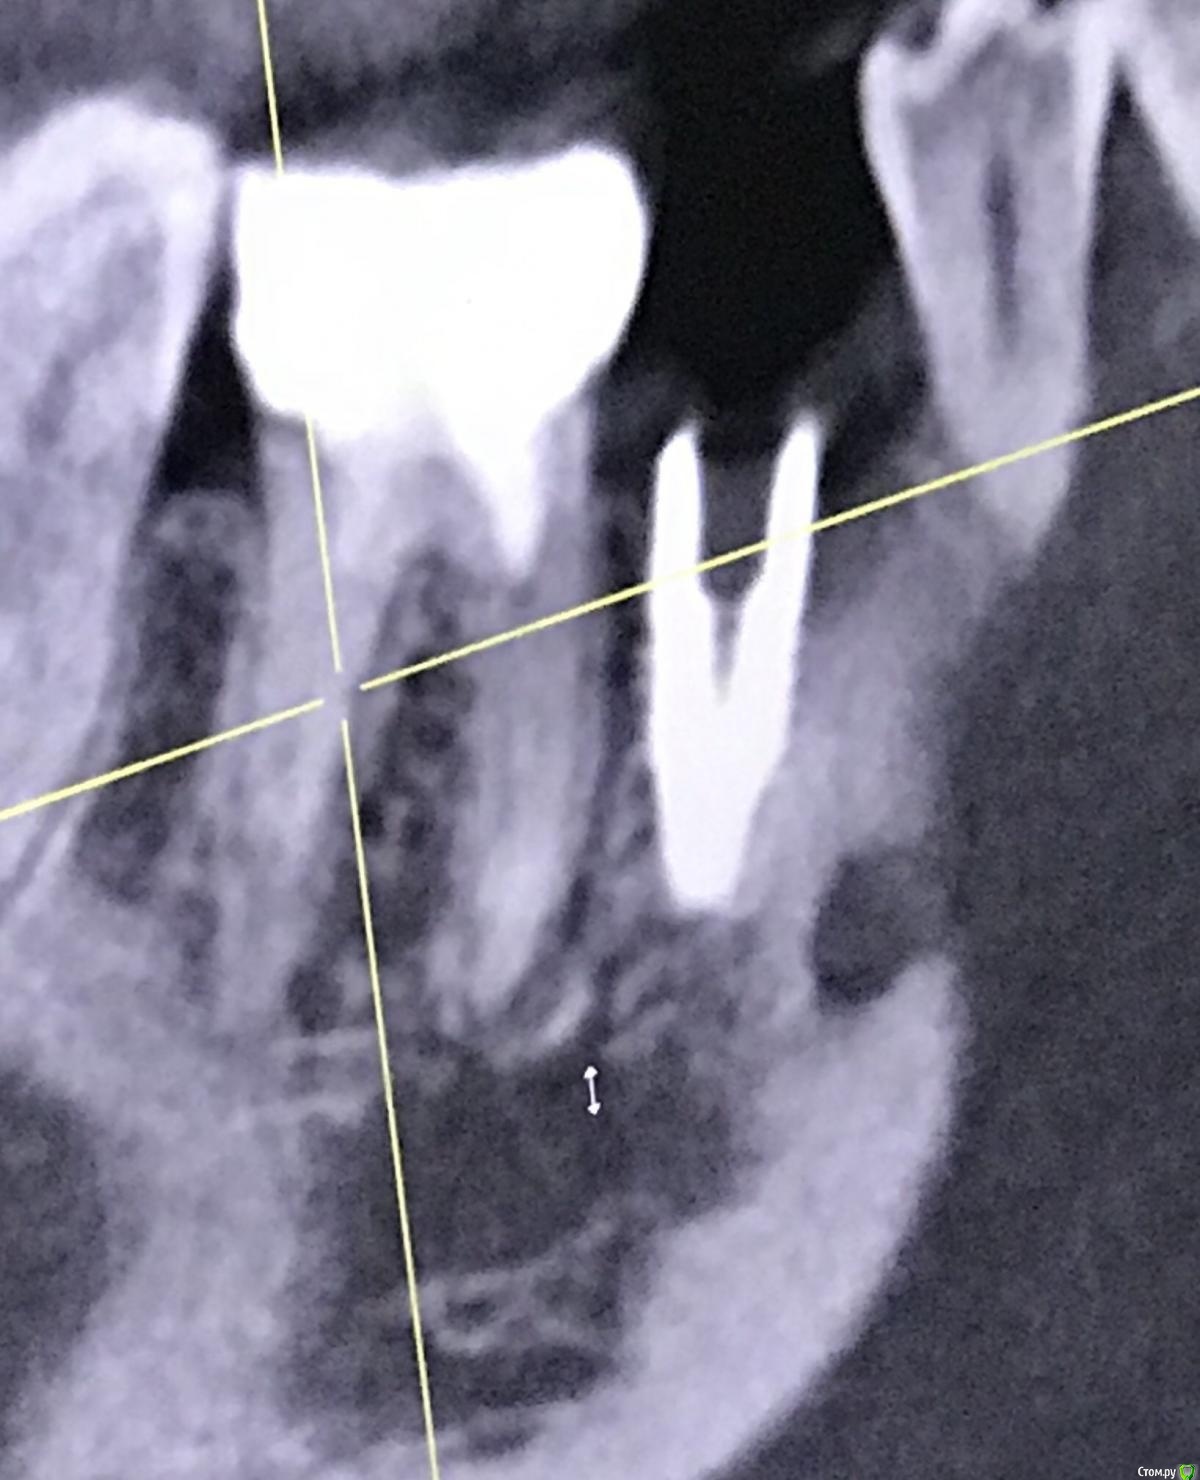

Irouil Опубликовано 26 декабря, 2020 Поделиться Опубликовано 26 декабря, 2020 Имплант запротезирован? Когда был установлен? Маловероятно, что описываемые жалобы связаны с имплантатом. Скорее причина в зубе - решение о его лечении лучше спросить в терапевтическом разделе, хирурги зубы не лечат. Если имплантат не запротезирован, то мне кажется логичнее его удалить - очень комрромиссно придется протезировать. Если уже есть коронка - нужен рентген с ней. 1 Ссылка на комментарий

111 Опубликовано 26 декабря, 2020 Автор Поделиться Опубликовано 26 декабря, 2020 (изменено) Iroil, спасибо большое за ответ.46 был кариес но не болел, периодонтита не было, никаких воспалений на верхушках не было. То есть 46 просто пролечили - обработали каналы, заложили кальций, и тд. Делалось под микроскопом, доктор очень хороший. По поводу 45 - изначально кости было достаточно по высоте, по объему пришлось подсыпать gen-oss 0,5 в момент имплантации, плюс сст с бугра. Вообще всё было хорошо, особо сильно не болело, без отёка зажило. В момент снятия швов - обнаружилась убыль кости в области 46, слегка оголился корень ближайший к 45, но мы как-то это не обсуждали с доктором. Установили Фдм, все ок.И вот пришло время ортопедии - это было летом 2019 - ортопед не захотел работать с имплантом, у которого на снимке оголена шейка. Десны достаточно при этом. Имплант не запротезирован.Спустя пару дней на визите у хирурга - я прошу выкрутить 45, мне отказывают, принято решение либо оставить как есть, либо подсыпать кости немного.Сейчас, декабрь 2020, я хожу с фдм и уже точно понимаю, что надо переустановить 45, но хирург предлагает 2 варианта:- оставить как есть и делать ортопедию (т.к. десна хорошая);- удалить 45 и 46 для создания удобного рабочего поля и имплантация 45, 46.Вот я пытаюсь понять, нельзя ли просто 45 выкрутить? Аккуратно удалить 45 не получится? (Очень не хочется расставаться с 46, сам по себе он не болит при накусывании и постукивании). Изменено 26 декабря, 2020 пользователем 111 Ссылка на комментарий